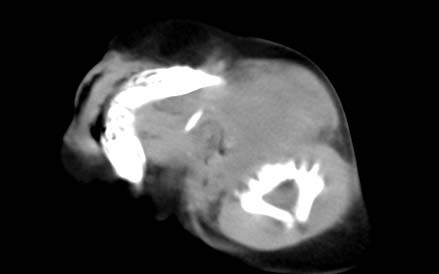

男,26天,发现左侧颈部包块5天,质较硬,患儿不哭不吵,无明显发热,头向右侧歪斜,其父母诉患儿出生时正常,昨天查血象wbc19.4×10的9次方/l,b超考虑来源于甲状腺的恶性肿瘤,我科认为肿块内有低密度区,而且病程发展较快,血象高,考虑炎性病变可能大。患儿年龄太小没做增强。请大家提出高见。

男,26天,发现左侧颈部包块5天,质较硬,患儿不哭不吵,无明显发热,头向右侧歪斜,其父母诉患儿出生时正常,昨天查血象wbc19.4×10的9次方/l,b超考虑来源于甲状腺的恶性肿瘤,我科认为肿块内有低密度区,而且病程发展较快,应该首先排除血肿,其次考虑感染

随访结果:炎症(患儿经过一星期抗炎治疗后颈部包块明显缩小,现已经正常)。